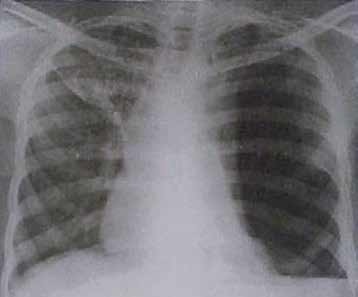

33 – Homem branco de 58 anos refere ter sido vítima de ferimento por arma branca há 2 horas. Foi atendido em Unidade Básica de Saúde onde teve seu ferimento suturado. Encontra-se hemodinamicamente estável com exame neurológico normal. O médico da UBS o encaminhou para o pronto-socorro do Hospital de referência para melhor avaliação. No PS, o paciente apresenta-se sem queixas além de dor no local da sutura. Observa-se ferimento de 2 cm no oitavo espaço intercostal esquerdo, na linha axilar média e que estava adequadamente suturado e com bom aspecto. Realizou o seguinte RX de tórax:

Nosso paciente foi vítima de ferida por arma branca em oitavo espaço intercostal esquerdo, na linha axilar média. Foi atendido inicialmente em uma Unidade Básica de Saúde, onde teve sua ferida suturada, e em seguida encaminhado ao pronto-socorro para avaliação. Exceto por dor local, encontra-se assintomático e hemodinamicamente

estável. Foi realizada radiografia de tórax, com presença de pneumotórax à esquerda, atelectasia total do pulmão esquerdo e desvio do mediastino para a direita. Com este desvio, o pneumotórax não deve ser considerado simples. Contudo, faltam manifestações clínicas para afirmarmos que este é hipertensivo, uma vez que o diagnóstico de pneumotórax hipertensivo é clínico. Agora, é

improvável que um indivíduo com uma radiografia como esta não tenha uma ou mais evidências clínicas de um pneumotórax hipertensivo, como hipotensão, turgência jugular, cianose, taquipneia etc. Sabemos também que o fechamento de uma ferida torácica é condição que pode levar a um pneumotórax hipertensivo. Foi, no mínimo, infeliz a escolha dessa radiografia para a questão. Há presença de nível líquido, o que deve ser imediatamente diagnosticado como um hemotórax.

32 – Homem branco de 58 anos refere ter sido vítima de ferimento por arma branca há 2 horas. Foi atenatendido em Unidade Básica de Saúde onde teve seu ferimento suturado. Encontra-se hemodinamicamente estável com exame neurológico normal. O médico da UBS o encaminhou para o pronto-socorro do hospital de referência para melhor avaliação. No PS, o paciente apresenta-se sem queixas além de dor no local

da sutura. Observa-se ferimento de 2 cm no oitavo espaço intercostal esquerdo, na linha axilar média e que estava adequadamente suturado e com bom aspecto. Realizou o seguinte RX de tórax:

Cite o (s) achado (s) radiológico (s).

Vítima de ferida por arma branca em oitavo espaço intercostal esquerdo, na linha axilar média, nosso paciente teve sua lesão suturada em uma Unidade Básica de Saúde. Foi encaminhado ao pronto-socorro para avaliação. De acordo com o enunciado, está assintomático. Foi realizada radiografia de tórax. O que identificamos na imagem? Bom, de início observamos um importante pneumotórax (setas amarelas), com atelectasia de todo o pulmão esquerdo. Há desvio da traqueia também. Podemos dizer que pelo desvio do

mediastino apresentado, este pneumotórax não pode ser considerado simples. Por outro lado, o diagnóstico de um pneumotórax hipertensivo é clínico. Mas, cá entre nós, com esse achado radiológico certamente deveríamos ter uma ou mais manifestações de pneumotórax hipertensivo, tais como, hipotensão, turgência jugular, taquipneia, cianose etc. Além disso, o fechamento completo de uma ferida torácica é condição que predispõe ao pneumotórax hipertensivo. Concluímos que o autor foi extremamente infeliz na escolha dessa imagem para o enunciado, uma vez que o paciente não

apresenta sintomas. Estamos lidando com uma “dissociação enunciado-radiológica”. Vamos continuar nossa análise. Além do pneumotórax, existe franco velamento do seio costofrênico esquerdo, o que representa um derrame pleural (seta azul). Sabemos que no trauma, todo o derrame pleural deve ser obrigatoriamente encarado como um hemotórax. Sendo assim, os principais achados radiológicos são de hemopneumotórax à esquerda e desvio do mediastino para a direita.